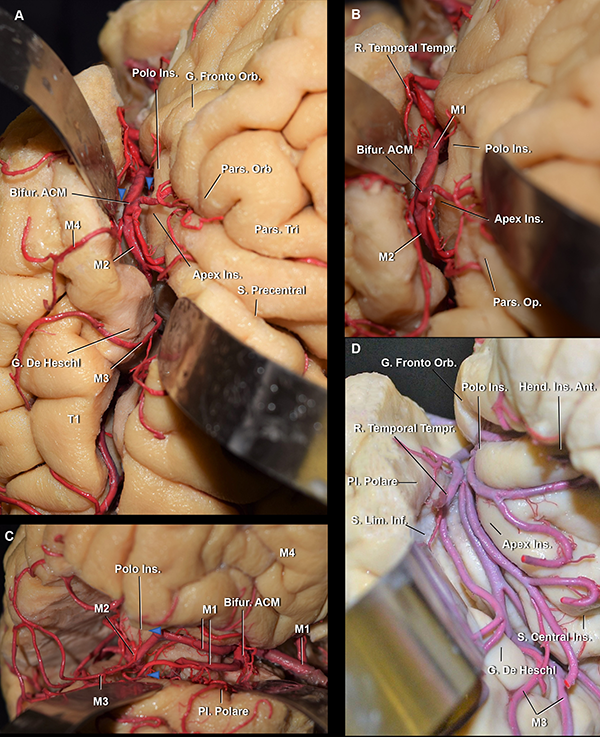

La FS se divide en una sección lateral y una basal. El punto divisor arbitrario entre ellas es el limen insular, definido como un área anatómica arqueada que se extiende desde el punto donde el giro largo insular posterior se fusiona con el plano polar del lóbulo temporal, hasta los giros fronto-orbitarios. El limen insular se relaciona superficialmente con el vértice inferior de la pars triangularis del giro frontal inferior. El mismo oficia como eje para el cambio de dirección de la arteria cerebral media (ACM) (Figura 1).

El tronco silviano se extiende hasta la punta inferior de la pars triangularis. En dicho vértice, se originan los tres ramos. Este punto es conocido como punto silviano anterior (Figura 3).

La parte profunda de la FS tiene una organización más compleja. La parte cisternal en la superficie basal del cerebro se extiende desde la estría olfatoria lateral hasta el limen insular (Figura 1A). Está compuesta por 1) el compartimiento opercular anterior, en un nivel intermedio de profundidad, y 2) la hendidura insular anterior y el compartimiento esfenoidal, en el nivel más profundo (Figura 1).

El compartimiento opercular anterior se define como el espacio entre los giros orbitarios posterior y lateral y el plano polar del lóbulo temporal (Figura 5A y 6B). Por otro lado, la hendidura insular anterior se localiza entre la ínsula y los giros orbitarios lateral y posterior (Figura 1C,6B,7A).

El compartimiento esfenoidal presenta una disposición de inferomedial a superolateral. El extremo medial del compartimiento está delimitado por la membrana aracnoidea silviana proximal, que lo separa de la cisterna carotídea y es perforada por el segmento proximal de M1 de la ACM (Figura 8B). La membrana aracnoidea silviana proximal está adherida a la estría olfatoria lateral y a la incisura rinal, o también llamada incisura temporal (Figura 1B y 8B). El segmento anterior del uncus se ubica medial a la membrana silviana proximal. El techo del compartimiento esfenoidal está compuesto por la sustancia perforada anterior (SPA) y los giros fronto-orbitarios. El núcleo caudado y lentiforme, así como también el brazo anterior de la cápsula interna, se localizan por encima del techo de este compartimiento. La pared posterior del compartimiento esfenoidal es el área donde la SPA se fusiona con el lóbulo temporal. El limen insular es su límite lateral (Figura 1A y B). El receso del limen, que es el área comprendida entre la arteria lentículo estriada más lateral y el limen insular, fue hallado en todos los hemisferios estudiados en este trabajo y midió un promedio de 12 mm de largo (Figura 1A). Este receso es un espacio desprovisto de arterias perforantes. El piso del compartimiento esfenoidal es el plano polar. Este compartimiento contiene principalmente: la mitad distal del segmento M1, las arterias perforantes de la SPA, las ramas corticales tempranas de la ACM, los troncos arteriales post bifurcación que pudieran nacer de este segmento si la bifurcación de la ACM fuera proximal al limen insular, la parte distal de la arteria recurrente de Heubner y la vena cerebral media profunda (Figura 1B y D).

Distalmente al limen insular, en la profundidad de los ramos superficiales, presentando una orientación diagonal, se localiza la parte cisternal lateral de la FS. Este segmento es también conocido como compartimiento operculoinsular lateral. Este compartimiento se encuentra compuesto por tres espacios estrechos: 1) el compartimiento opercular lateral, entre el opérculo frontoparietal y temporal, en un nivel intermedio, 2) la hendidura insular lateral y 3) la región retroinsular (Figura 6). Los últimos dos espacios se encuentran en el nivel más profundo de la cisterna silviana. La hendidura insular lateral se localiza entre la ínsula y los opérculos, extendiéndose desde el limen insular hasta el punto en el que los surcos limitantes insulares superior e inferior se conectan, punto conocido como punto insular posterior. Dicha hendidura tiene un bolsillo superior e inferior. La región retroinsular se extiende desde el punto insular posterior hasta el extremo distal de la FS. Esta región se relaciona superficialmente con el giro supramarginal, superiormente, y los giros temporales transversos, inferiormente (Figura 6B).

Figura 9: A. Vista latero superior, quirúrgica, de una FS izquierda (mismo espécimen que en Figura 1B y C). Cabeza de flecha azul: limen insular. El limen insular se encuentra medial y anterior a la punta de la pars triangularis. A su vez, el polo insular se encuentra superolateral al limen insular y el ápex insular, superolateral al polo. Cuanto más posterior en la cisterna silviana, más profundo es el compartimiento opercular. Posterior al giro de Heschl, el opérculo temporal tiene una dirección recta en el plano axial, haciendo más dificultosa la apertura de la FS. B. Vista aumentada de A. C. Vista anterolateral de un hemisferio derecho. El opérculo frontoparietal fue removido. La bifurcación de la ACM se localiza proximal al limen insular (cabezas de flecha azul). D. Vista superolateral del mismo espécimen que en Figura 1D y 7. Las ramas corticales tempranas de la ACM pasan por el limen insular, así como los troncos postbifurcación. Ins: insular; G: giro; Bifur: bifurcación; S: surco; Orb: orbitalis; Fronto Orb: frontoorbitario; R: ramo; Tempr: temprano; Op: opercularis; Tri: triangularis; Pl: plano; Lim: limitante; inf: inferior.

La ACM se divide en 4 segmentos: M1 (esfenoidal), M2 (insular), M3 (opercular) y M4 (cortical).

El segmento M1 se origina en la cisterna carotídea y se relaciona superiormente con la SPA e inferiormente con el segmento anterior del uncus (Figura 1D). Este segmento perfora la membrana silviana proximal y entrando al compartimiento esfenoidal de la cisterna silviana. En este segmento, se identificaron el origen tanto de las arterias lenticuloestriadas como de las ramas corticales tempranas (Figura 1C y D). En nuestra serie, 9 de los 10 hemisferios presentaron por lo menos una rama cortical temprana.

El segmento M2 comienza en el punto en donde el segmento M1 cambia de dirección. Este punto se conoce como la rodilla o genu de la ACM y se localiza en el limen insular (Figura 9). El segmento M1 tiene una orientación mediolateral, perpendicular al punto de vista del neurocirujano; el segmento M2, una orientación inferosuperior, paralela al punto de vista del neurocirujano (Figura 10C). Durante la cirugía, una manera de diferenciar el segmento M1 de M2 es observando su dirección. El 80% de las bifurcaciones de la ACM se localizaron en o proximal al limen insular.

Durante la cirugía, con la membrana aracnoidea intacta, no es fácil identificar las estructuras anatómicas como se hace en los especímenes cadavéricos disecados. Es por esto que los cirujanos pueden usar como punto de referencia para localizar al punto silviano anterior al área más prominente y anterior del giro frontal inferior que se continúa, luego de un borde agudo, con la superficie basal del cerebro. Esta área prominente es la pars orbitalis (Figura 9A). Los giros frontoorbitarios y la superficie basal de la FS solamente son expuestos luego de que el ala menor del esfenoides es removida. Unos pocos milímetros posteriores a esta área, uno puede asumir con seguridad que se localiza la pars triangularis. Más aún, la punta de la pars triangularis suele apuntar a un ensanchamiento prominente de la FS: el punto silviano anterior (Figura 3). También, dado que el punto silviano anterior se localiza donde la fisura silviana pasa de la superficie basal a la lateral, ubicar el sitio donde la fisura cambia de sentido, es otra forma de encontrar este punto microquirúrgico. Finalmente, cuando la parte superficial de la FS está deformada porque el opérculo frontal indenta al temporal, o viceversa, o, cuando la membrana aracnoidea es particularmente opaca, el neurocirujano debe localizar la unión de la vena superficial temporal con la frontal. Este punto es nombrado en la literatura como “confluencia venosa silviana”. El punto silviano anterior se localiza unos milímetros proximales a la confluencia venosa silviana (Figura 8B y 10A).

Los autores comienzan a disecar la FS en el punto silviano anterior debido a que allí se encuentra una “subcisterna” aracnoidea natural generada por una retracción espontánea de la punta de la pars triangularis (Figura 5A). Además, la orientación oblicua inferior en el plano coronal del plano polar del lóbulo temporal (Figura 11C y D), así como también, su dirección lateromedial, contribuyen a la amplificación del espacio subaracnoideo en este punto microquirúrgico esencial. Para acceder a las cisternas aracnoideas basales, la fisura es disecada desde la superficie lateral a la basal. Solo cuando es necesario, las cisternas carotídeas, interpeduncular y quiasmática son abiertas previamente. Esto es útil, por ejemplo, cuando hay hipertensión intracraneal debido a la ruptura de un aneurisma, y se precisa bajar la tensión para realizar la disección. Debe ser tenido en cuenta que para liberar una cantidad considerable de líquido cefalorraquídeo (LCR) con este propósito, es recomendable abrir la cisterna carotídea, así como también la interpeduncular, a través de la disección de la membrana de Liliequist. La cisterna carotídea es una cisterna relativamente pequeña, que, si es abierta aisladamente, solo liberará una pequeña cantidad de LCR.

El primer compartimiento silviano que es disecado desde el punto silviano anterior es el compartimiento opercular anterior. La mayoría de las FS tienen un compartimiento opercular anterior curvilíneo irregular. Esto se debe frecuentemente a una pars orbitalis prominente que indenta y comprime al plano temporal. Una vez que este compartimiento es disecado, si el cirujano continúa proximalmente y en profundidad por la fisura, se accede al compartimiento esfenoidal. Con una cánula de aspiración delicada con mínima presión de succión, pinzas bipolares bayonetada y microtijeras, se progresa la disección.

Las ramas y segmentos de la ACM no siempre se identifican con claridad. En función de poder hacerlo, es útil disecar los vasos arteriales desde distal a proximal hasta que la bifurcación carotídea es identificada, y luego seguir a la ACM en dirección opuesta, de proximal a distal. M1 debe ser disecada por su cara anterior. Esto es porque las arterias lenticuloestriadas usualmente nacen de su cara superior o posterosuperior (Figura 1C,10C, 10D).

Si la superficie lateral de la FS necesita ser abierta, la disección continua distalmente. La técnica microquirúrgica es la misma que la descripta. El limen insular y la bifurcación de la ACM sirven como un punto de referencia confiable para comenzar a disecar al lóbulo insular, de anterior a posterior. El limen insular es un área donde se pueden encontrar muchos vasos arteriales. No solo los troncos superior e inferior de M2 se localizan aquí, sino también, las ramas corticales tempranas tienen su curso. Los opérculos son separados utilizando presión suave con la pinza bipolar y la cánula de aspiración delicada, siempre con la ayuda de algodones pequeños y, también, de microtijeras. A medida que los opérculos son disecados, se puede introducir algodones para gradualmente abrir el compartimiento operculoinsular lateral sin gran presión, hasta que toda la extensión de la fisura es disecada.

El giro frontal inferior se divide por los ramos superficiales de la FS, de anterior a posterior, en la pars orbitalis, la triangularis y la opercularis (Figura 3 y 5A).

La pars orbitalis se continua basalmente con los giros orbitarios lateral y posterior. Es el área más prominente del giro frontal inferior (Figura 5A y 9A)22 y se relaciona superficialmente con el keyhole (agujero de trépano llave) del abordaje pterional.

La pars triangularis, que posee una forma de “V”,22,23 suele albergar un ramo originado del surco frontal inferior y cubre al ápex insular. Por otro lado, la pars opercularis, que tiene forma de “U”,22 alberga un ramo originado del surco precentral, o en su defecto, al extremo inferior del surco precentral (Figura 3 y 5). La pars opercularis, se recuesta superficialmente sobre el giro corto posterior de la ínsula (Figura 4A). Más aún, la rodilla de la cápsula interna y el foramen de Monro se ubican en la profundidad de dicho giro corto (Figura 12B). Finalmente, el área de Broca del lenguaje, se compone de la pars triangularis y opercularis del hemisferio dominante.22

El plano polar es un área integrada por giros cortos oblicuos menores: los giros de Schwalbe (Figura 6B).25 Por un lado, tiene una orientación lateromedial en el eje axial, escondiendo su punta anterior debajo del giro orbitario posterior (Figura 6).15 Por otro lado, tiene una orientación oblicua inferior en el eje coronal, que contribuye al agrandamiento del espacio subaracnoideo en el punto silviano anterior.22,23

El polo insular es definido como la región más anteroinferior de la ínsula. Está localizado lateral al limen insular (Figura 4A, 4C, 7C). El límite medial de la superficie anterior es el surco limitante anterior de la ínsula (Figura 4A y B).

El limen insular es un área anatómica arqueada, medial al polo insular, que yace sobre al fascículo uncinado y se extiende desde el punto en el que el giro largo insular posterior se encuentra con el polo temporal, hasta los giros frontoorbitarios (Figura 13A). El fascículo uncinado (FU), junto con el fascículo fronto-occipital inferior (FFOI) componen la parte ventral de la cápsula externa. El FFOI está constituido por fibras que conectan a los giros frontales medio e inferior con el lóbulo occipital. Las fibras del FFOI comienzan en el lóbulo frontal, en un plano profundo al FA, pasa profundo al punto insular anterior, posterior al FU y luego, cursando a través del giro temporal superior y medio, alcanza la parte posterior de los lóbulos parietal y occipital. El FU conecta estructuras temporales y frontales paralímbicas: el polo temporal con las áreas orbitofrontales y septal (Figura 13).24

Tanriover et al.26 observa que entre la arteria lenticuloestriada más lateral y el limen insular hay un espacio de 15mm promedio desprovisto de arterias perforantes. Esta área es nombrada como receso del limen. En nuestros hemisferios, fue de 12 mm promedio.

Existe un consenso a lo largo de la literatura de que la bifurcación silviana se localiza más frecuentemente en el limen insular. Según Rhoton,12 Gibo3 y Wen,15 86-90% de las bifurcaciones se localizan proximal al o en el limen insular. Sin embargo, Türe,27 reporta en su serie que 57.5% de las ACM se bifurcan en el limen, 15% 5 a 8 mm proximal al, y 27.5% 4 a 10 mm distal al limen insular. Finalmente, Yasargil17 considera que en el 50% de los casos, M1 se divide en el limen insular. En nuestra serie, en el 50% de los casos la bifurcación de la ACM se localizó proximal al, 30% en, y 20% distal al limen insular. Así también, la presencia de ramas corticales tempranas en el 90% de nuestros especímenes, se correlaciona con el 91% publicado por Tanriover et al.26 Definimos a las ramas corticales tempranas, como aquellas arterias nacidas en M1 que no tienen relación estrecha con la corteza insular e irrigan áreas corticales temporales o frontales.

La bifurcación carotídea se relaciona con el ápex uncal y el segmento proximal de M1 se relaciona inferiormente con el segmento anterior del uncus. Más aún, el genu de M1 se localiza en el limen insular, por lo tanto, en una AD, marca el borde anterior de la ínsula. La pars triangularis está ubicada unos milímetros distales al genu de M1. Dado que el giro precentral cubre el tercio medio de la ínsula, se puede inferir que el giro precentral en una AD se localiza en el punto medio del triángulo silviano. Finalmente, el extremo posterior del lóbulo insular se localiza en el punto M. Consecuentemente, lesiones vascularizadas localizadas en el genu de M1, son encontradas unos pocos milímetros proximales a la pars triangularis, cerca del polo insular; lesiones localizadas inmediatamente distal al genu, se relacionan superficialmente con la punta de la pars triangularis; y aquellas posicionadas en el punto medio entre el genu y el punto M, son mediales al giro precentral (Figura 11A y B).15